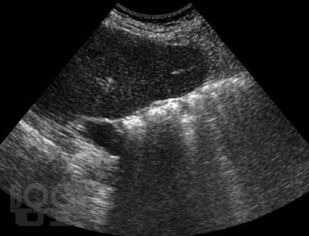

В данном пособии систематизированы сведения об артефактах, которые имеют место при выполнении ультразвуковых исследований. Отдельно рассмотрены эффекты, возникающие в режиме серой шкалы и при выполнении допплеровских исследований. Представлены разработки авторов по изучению допплеровского «мерцающего артефакта» и акустических потоков. Даны рекомендации, позволяющие уменьшить отрицательное влияние артефактов на качество диагностического изображения.